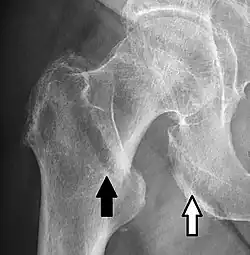

In projectional radiography, visual artifacts that can constitute disease mimics include jewelry, clothes and skin folds.[7]

- A hip fracture (black arrow) next to a skin fold (white arrow)